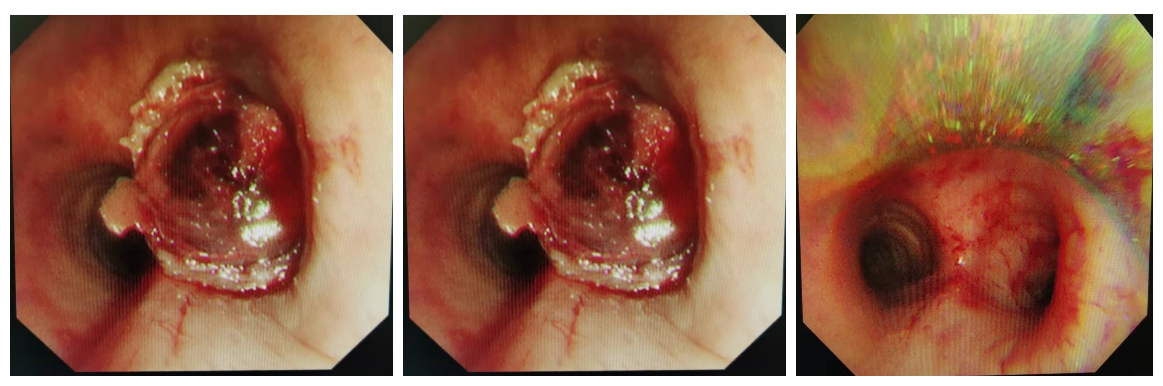

气管镜下见气管、右主支气管新生物 术后气道恢复通畅

次日,吴先生已在手术室内完成全麻。术中,呼吸科、麻醉科和手术室医护互相配合,在硬镜下为病人进行气道内探查。硬镜下可见气管下段的新生物堵塞约90%的管腔,而右主支气管管腔已被完全堵塞。蒋主任团队在气管镜下对新生物进行圈套、切除,术中仅有少量出血,共取出3块新生物组织送病理检查,术后再次探查见气管、右主支气管管腔已恢复通畅。